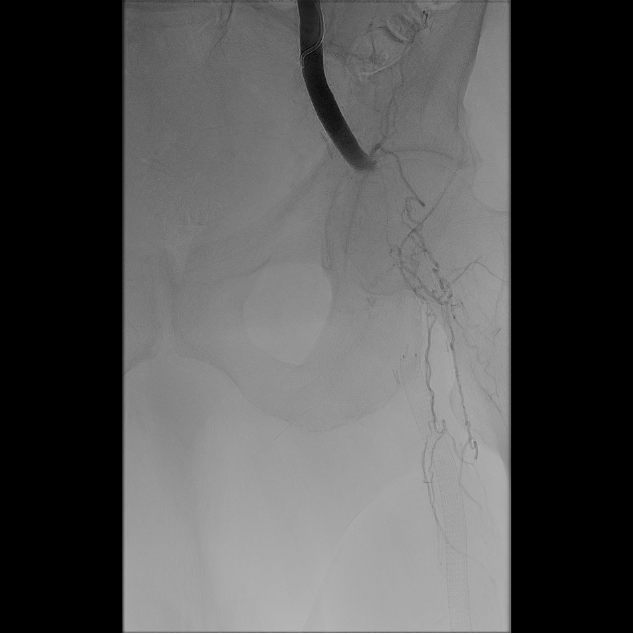

Based on his comorbidities, history of recurrent stenting of the left SFA, and an occlusion of the SFA over 200 cm, he was deemed to be an appropriate candidate for percutaneous transmural arterial bypass (PTAB). However, in order to establish long-term patency, we proceeded to gain posterior tibial artery access to identify a 3-vessel runoff (Figure 2). With this information, using the outline of the stents in left SFA and using a 0.018-in Glidewire Advantage (Terumo) and a 0.018-in Rubicon catheter (Boston Scientific), we were able to obtain access into the left profunda femoral artery (Figure 3). Despite multiple-balloon angioplasty, the recoil within the left common femoral artery (CFA) left little option but to place a 7.0-mm Eluvia stent (Boston Scientific), which was overlapped with the proximal stent in the left SFA (the profunda femoral artery was patent after balloon angioplasty; Figure 4).